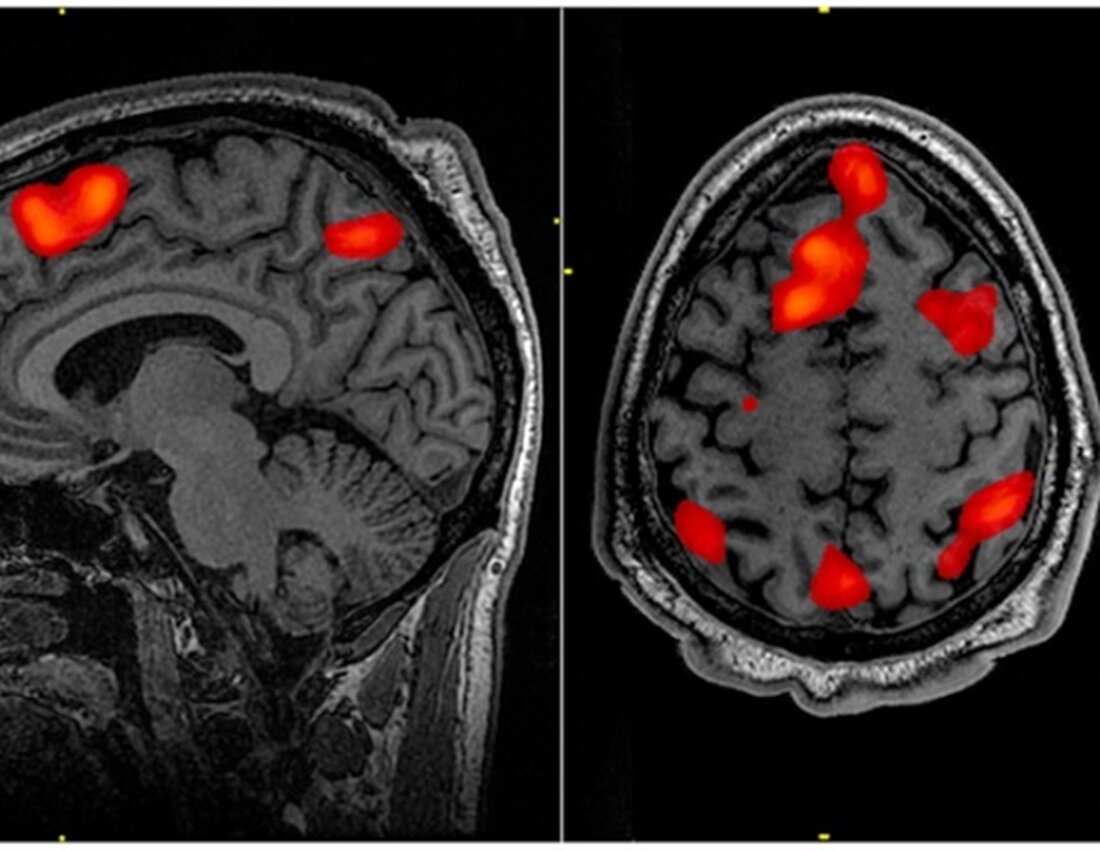

Forscher am Albert Einstein College of Medicine haben jetzt von den National Institutes of Health (NIH) ein fünfjähriges Stipendium in Höhe von 3,4 Millionen US-Dollar erhalten, um die Kompromisse zwischen den aeroben Vorteilen des Fußballs für das Gehirn und den negativen Auswirkungen des Kopfballspiels in einer Studie zu untersuchen, bei der Neuroimaging und Belastungstests zum Einsatz kommen und kognitive Tests.

An der neuen Studie werden 280 junge Männer und Frauen teilnehmen – eine Gruppe bestehend aus 140 Fußballspielern mit hoher (70) und geringer (70) Belastung durch Kopfball, 70 Nicht-Kollisionssportlern und 70 Nichtsportlern. Zu Beginn der Studie und erneut zwei Jahre später werden die Teilnehmer getestet, um ihre aerobe Kapazität zu messen, sich MRT-Gehirnscans unterziehen, um ihre Struktur der weißen Substanz zu bestimmen, und detaillierte Umfragen und Tests durchführen, um ihren kognitiven Status zu beurteilen. Anhand ihrer Ergebnisse werden Dr. Lipton und seine Kollegen feststellen, ob die aeroben Vorteile des Fußballs den Schaden ausgleichen, der durch das Kopfballspiel entsteht. Die Forscher werden auch untersuchen, ob genetische Faktoren und das Geschlecht individuelle Unterschiede in den Ergebnissen erklären können.